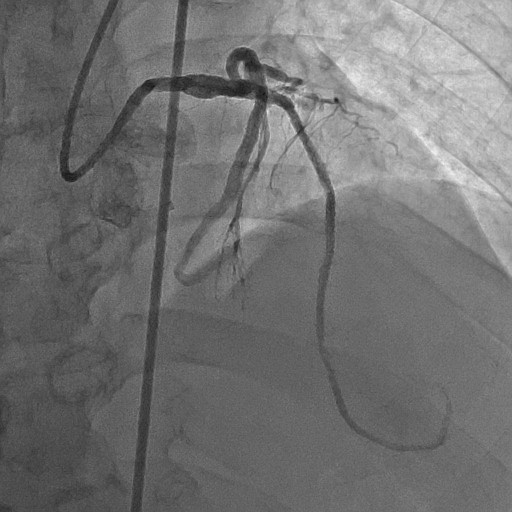

Re-attempted PCI for LAD CTO was planned. The procedure was performed with an 8-Fr, SPB 3.5 SH for the antegrade approach and a 6-Fr IMA for retrograde angiography. Primary antegrade approach was performed because there were no feasible collateral channels. Gaia Next 3 could penetrate the proximal cap of CTO. Since Gaia Next3 could not proceed into the CTO mid portion, the guide wire was escalated to Gaia Next 4. However, Gaia Next 4 advanced into extra plaque space beyond the CTO distal true lumen angiographically. Therefore, we decided to perform tip-detection (TD) method using intravascular ultrasound (IVUS). IVUS revealed that the guide wire proceeded into extra plaque from the CTO proximal portion, although the CTO entry was in the intra plaque space. At first, we tried TD-intra plaque tracking (IPT) in the CTO body. However, Conquest Pro 12 ST (CP-12ST) could not penetrate the CTO body. Therefore, we performed TD-antegrade dissection andreentry (ADR). Eventually, CP12 ST succeeded to puncture the distal true lumen supported by a Caravel. We implanted a drug-eluting stent, which resulted in successful revascularization.